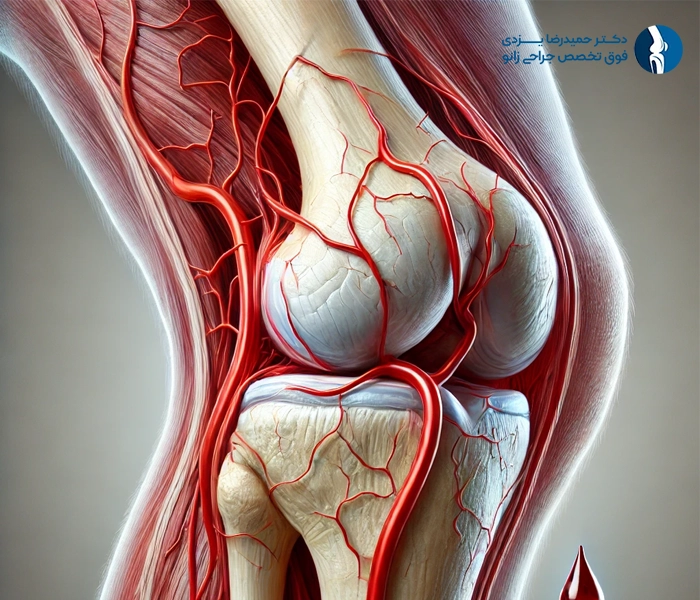

آرتروسکوپی زانو یک روش جراحی کمتهاجمی است که برای تشخیص و درمان مشکلات مفصل زانو به کار میرود.

3.آسیب عصبی یا عروقی

هرچند نادر است، اما ممکن است در حین جراحی، اعصاب یا عروق خونی اطراف زانو آسیب ببینند. این آسیبها میتوانند منجر به بیحسی، ضعف عضلانی یا مشکلات گردش خون شوند. انتخاب جراح با تجربه و مهارت بالا میتواند خطر این عوارض را کاهش دهد.